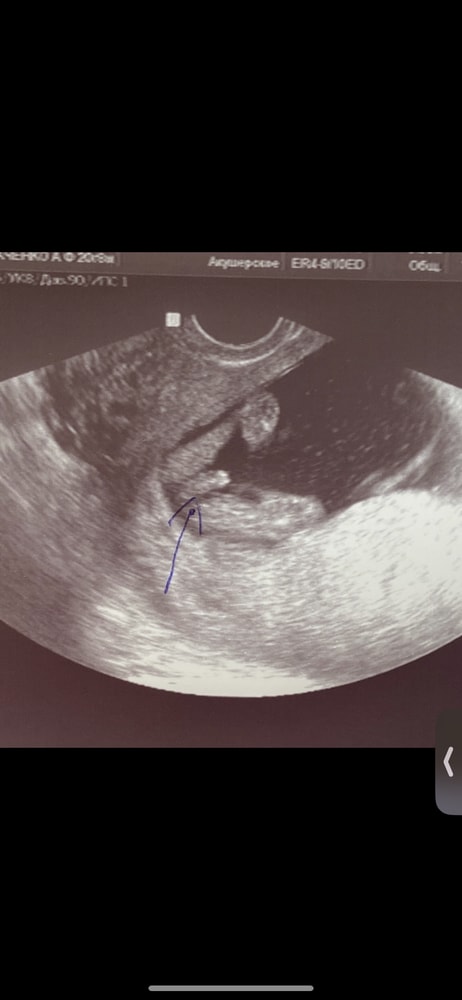

Алёнка, ну прям заметная разница с моим фото)

Значит, всё же девочка))

15 недель мальчик)